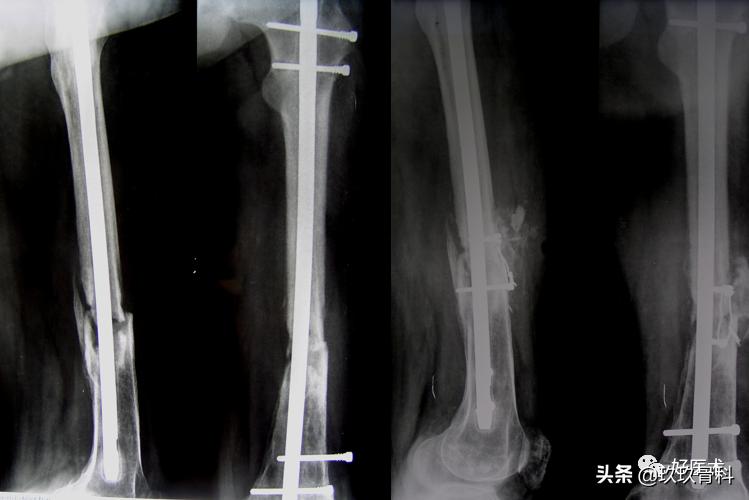

(三)胫骨髓内钉手术指征

1.实心钉:

- Gustilo Io、IIo开放Frx

- 高能量不稳定闭合Frx

- 髓腔小的粉碎Frx

- 部分峡部远、近端Frx

2.空心钉:

- 骨干的开放骨折

- 骨干的闭合骨折

- 部分峡部远、近端的骨折

- 畸形愈合

- 不愈合

胫骨髓内钉插入技术

1)顺行胫骨髓内钉进针点

- 在髓腔的中心线上

- 胫骨平台前缘

- 尽可能高

- 不损伤平台

2)顺行胫骨髓内钉进针点

- 最大限度屈膝

- 切口胫骨结节-髌骨下极沿髓腔方向

- 打开髓腔:导针与胫骨干纵轴矢状面呈15°

- 影像增强仪检查位置